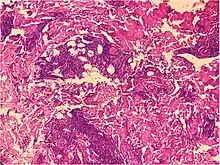

Psoriaform dermatitis

Examining multiple deeper levels is recommended if initial cuts do not correlate well with the clinical history.[2]

Psoriaform dermatitis typically displays:[2]

- Regular epidermal hyperplasia, elongation of the rete ridges, hyperkeratosis, and parakeratosis.

- Usually:A superficial perivascular inflammatory infiltrate

- Often: Thinning of epidermal cells overlying the tips of dermal papillae (suprapapillary plates), and dilated, tortuous blood vessels within these papillae

Further histopathologic diagnosis is performed by the following parameters:

| Mycosis fungoides | Present | Focal | Regular or irregular | Normal | Normal | Minimal or no spongiosis; ±Pautrier microabscess | Atypical lymphoid cells lining the dermo–epidermal junction | ![]() Pautrier microabscesses |